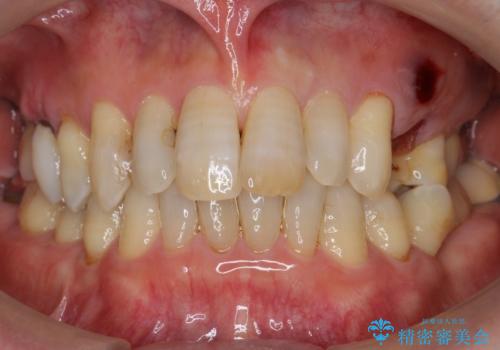

歯がわれた 抜歯してインプラント 50代男性

- 歯ぐきの腫れと痛みを主訴に来院された患者様です。

精査したところ、歯が割れており保存不可能な状態であったためやむなく抜歯しました。

患者様のご希望によりインプラント治療を行いました。